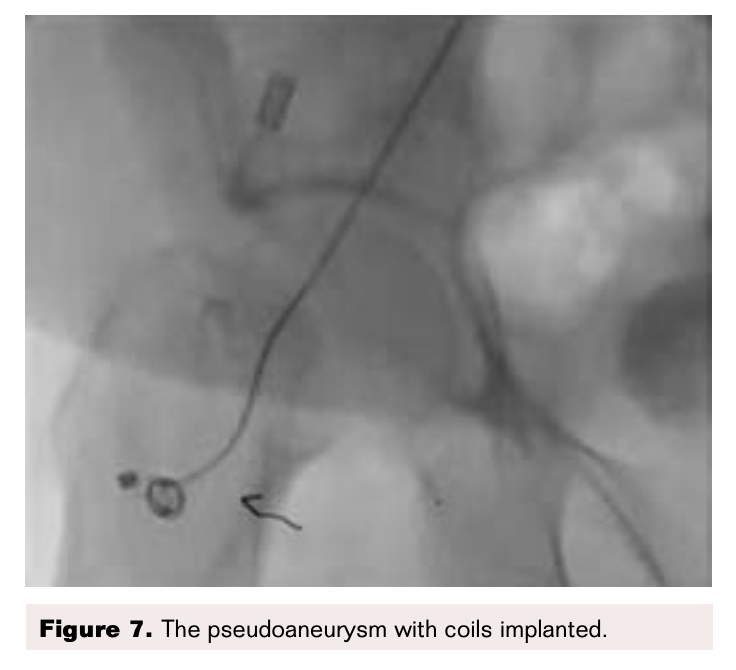

At SCTIMST, ultrasonic guided manual compression was performed for 60 minutes. However, flow into the pseudoaneurysm continued. The patient was then taken for percutaneous coil insertion under fluoroscopic guidance (Cook Nestor; coils 0.035). A left femoral puncture was taken and a check angiogram was performed (Figure 6). This revealed a bilobed pseudoaneurysm arising from the right common femoral artery. Through a guide catheter, Cook coils were instilled using a guidewire (Figure 7). However the check angiogram showed continued blood flow into the aneurysm (Figure 8). Hence it was decided that the sac would be closed by instillation of thrombin percutaneously.